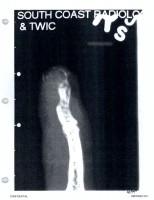

Plt144 | Finger Picture | 2015-03-08 | both parties (Days 06, 14, 20) | graphic, so link only | graphic, so link only | |

Plt145 | Finger Picture | 2015-03-09 | team JD (Days 06, 14) | |||

Def369 | Photos - finger | 2015-03 | team AH (Day 20) | according to Mr. Rottenborn already in evidence, can't find when it was used before, but if so, it was not uploaded | the published photos are pages 12 and 26 of the exhibit | |

Plt45 | 3/8/15 Gold Coast Hospital Record | 2015-03-08 | --- | --- | --- | Partial duplicate - contained in Def360 ------- BN presumably DEPP11506 |

Def359 | Email and finger photos - Kipper to Deuters, 3/8/15 | 2015-03-08 | --- | --- | --- | |

Def370 | Email - Raja Sawhany notes re finger injury, 3/8/15 | 2015-03-08 | team AH (Day 03) | not published to the jury, not in evidence due to objection | --- | |